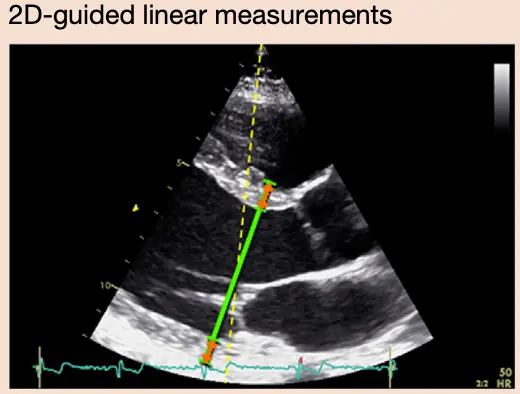

Measuring LV size

Linear Measurements

- Linear internal measurements of the left ventricle and its walls be performed in the parasternal long-axis view.

- Values should be carefully obtained perpendicular to the LV long axis and measured at or immediately below the level of the mitral valve leaflet tips.

- You want to be perpendicular to the LV long axis, i.e. in line with the flow of blood